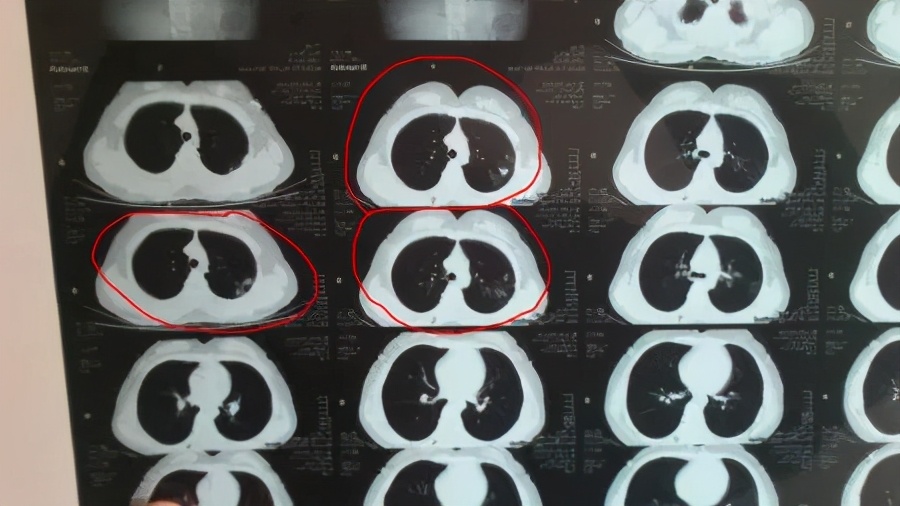

(资料图)图文无关

我仔细比对了他的所有检查结果,发现肺部这个阴影几年来都很稳定,查了痰,结果阴性。经过各种细致的比对和检查,我判断,这应该是陈旧性结核病,也就是说,小伙子确实“不知不觉”地得过肺结核,但又自愈了,现在也没有传染性。